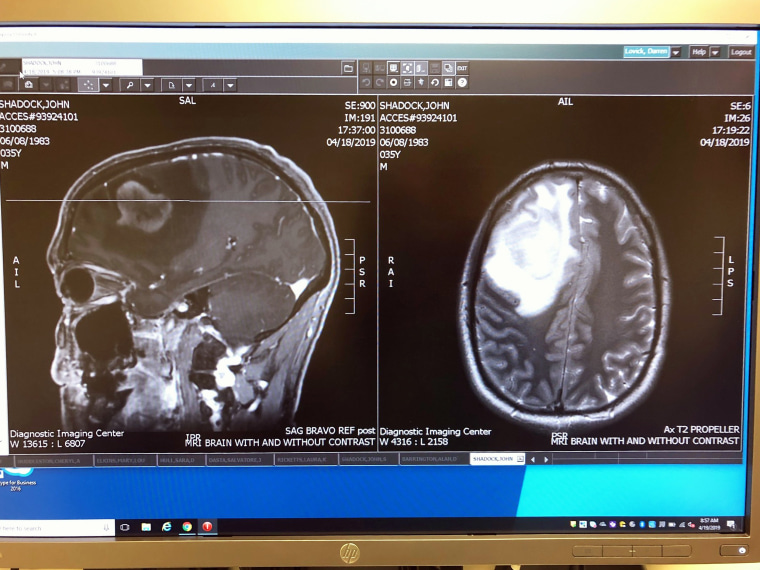

Their primary care physician referred John Shadock for a brain scan in April 2019. At the imaging center in Kansas City, Missouri, where the couple lived at the time, they watched other people leave right after their scans, but they were asked to stay.

“It was a younger doctor, and he looked like he’s about to cry. He said, ‘There’s something in your head that looks like a big tumor. You have to leave here and immediately go to the emergency room.’”

Five days later, John Shadock was on an operating table, undergoing his first brain surgery. A biopsy of the tumor confirmed it was glioblastoma, “one of the most complex, deadly and treatment-resistant cancers,” the National Brain Tumor Society warns. It’s so aggressive that it’s been called “the terminator.”